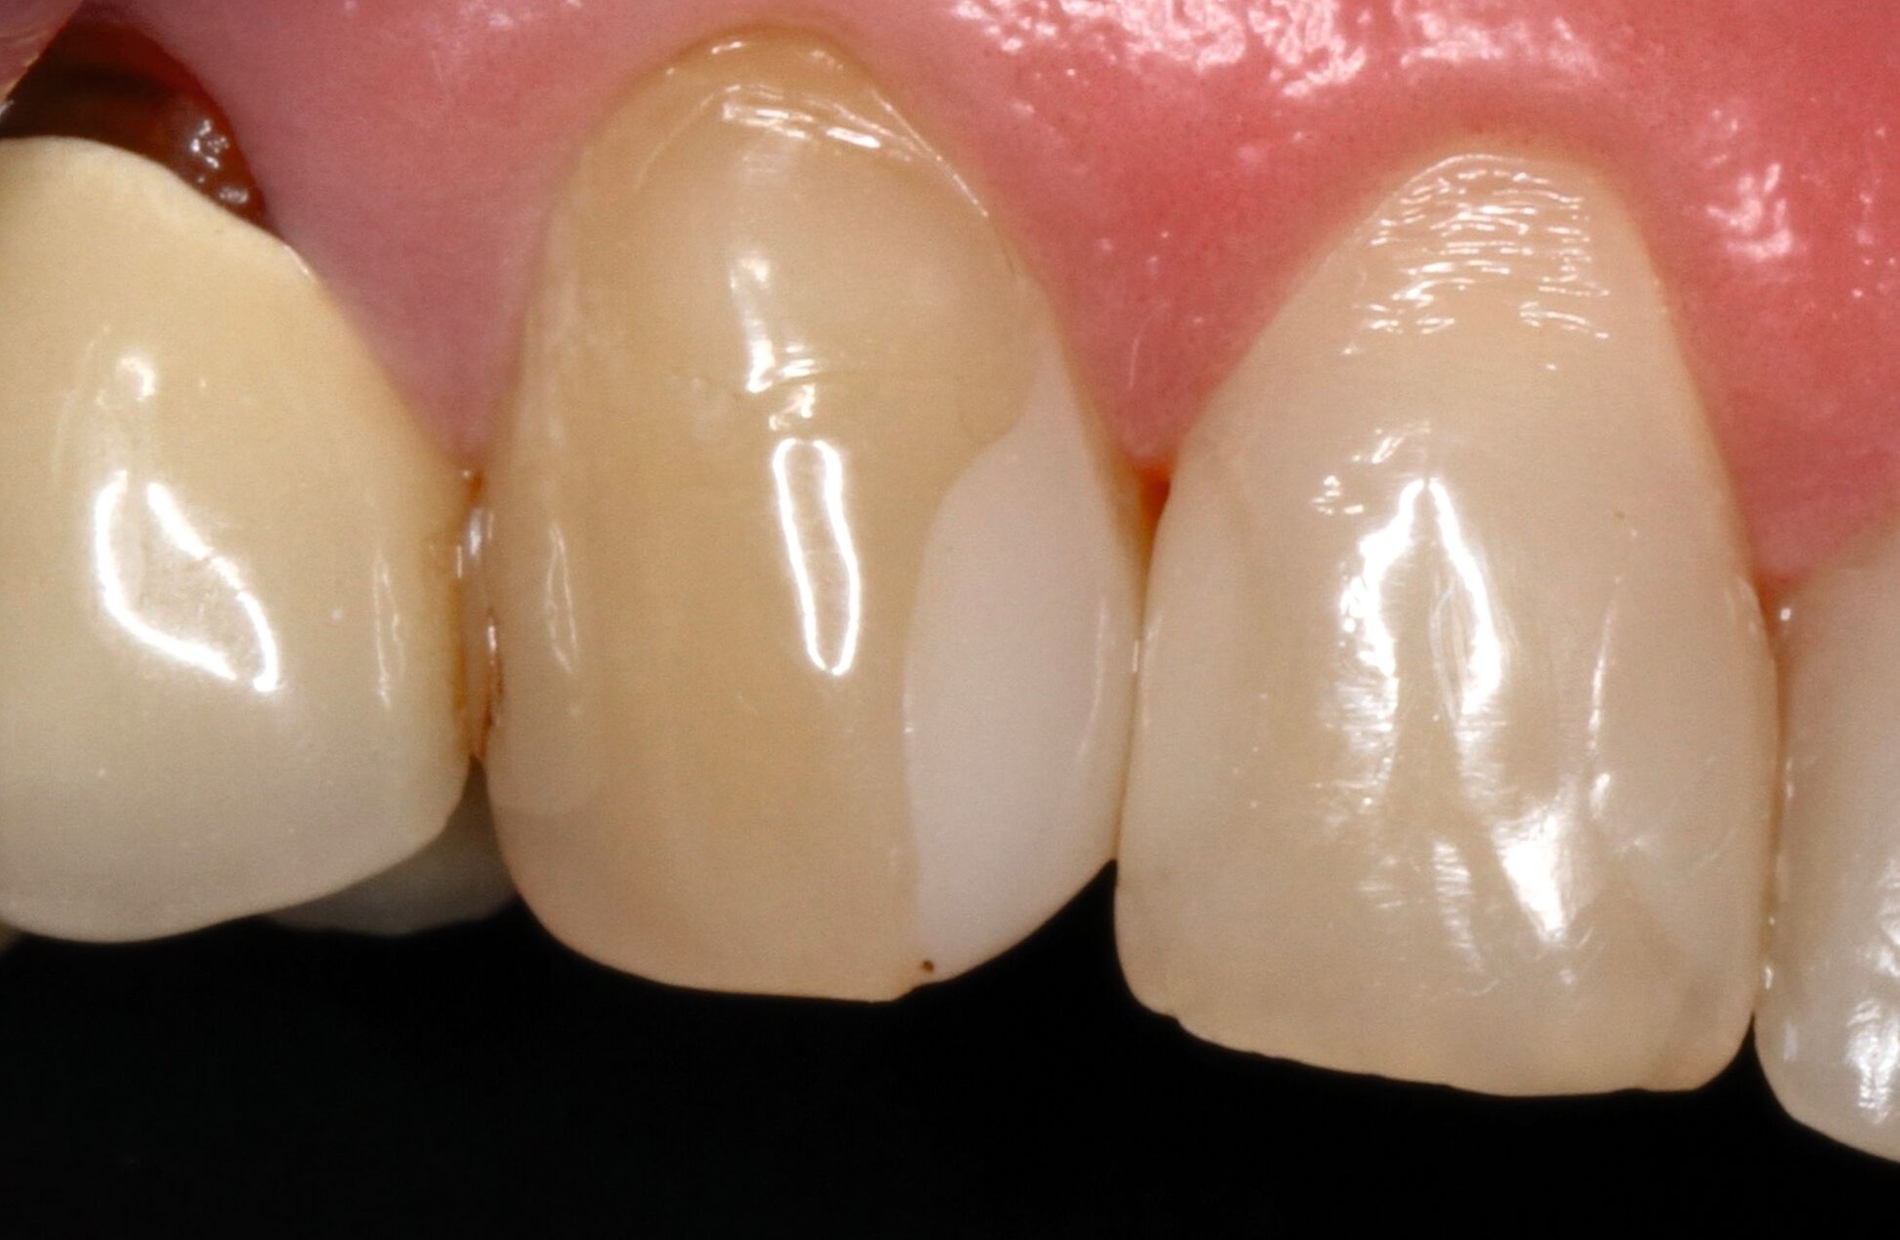

Die dentale Ausgangssituation zeigte im Seitenzahnbereich ein suffizient konservierend und prothetisch versorgtes Gebiss der zweiten Dentition sowie im Frontzahnbereich nicht kariogene Zahnhartsubstanzverluste und eine defekte Krone mit Sekundärkaries (Abbildungen 1 und 2).

Zur Verbesserung der Ästhetik und des Wohlbefindens des Patienten standen die Harmonisierung der Lachlinie und des Frontzahnbogens sowie Farb- und Formkorrekturen der Oberkieferfrontzähne im Fokus. An den Zähnen 11 und 21 waren Zahnhartsubstanzverluste durch Erosion und Attrition zu erkennen. Zahn 23 hatte ebenfalls einen erosiven Defekt, Zahn 13 eine farblich abweichende Kompositrestauration und die Zähne 14 und 24 wiesen keilförmige Defekte zervikal der Kronenränder auf, die einen suffizienten Randschluss haben (Abbildung 1a).